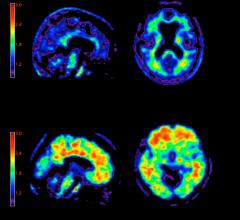

June 1, 2020 — TAUVID, a radioactive diagnostic agent, has been approved by the FDA for positron emission tomography ...

Eli Lilly and Co. and Avid Radiopharmaceuticals Inc. announced a Phase 3 study of positron emission tomography (PET) imaging agent flortaucipir F-18 met its two primary endpoints, defined as predicting brain tau pathology and predicting Alzheimer's disease diagnosis.

The U.S. Food and Drug Administration (FDA) has approved the first diagnostic agent to image Alzheimer’s disease beta-amyloid neuritic plaques in the living brain. Previously, the only way to confirm diagnosis of these plaques was from post-mortem biopsies. Eli Lilly and Company and Avid said the FDA cleared the commercial release of florbetapir (Amyvid).